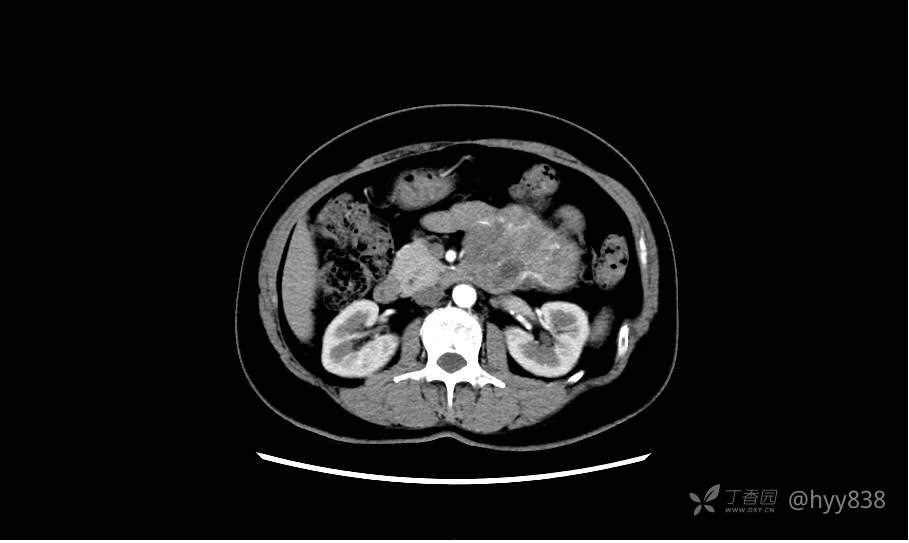

静脉期(机器故障---延迟期了)